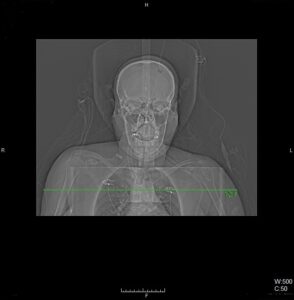

Topogram AP

Topogram Lateral

Topogram Parameters

Topogram (AP)

- Topogram length: 512Ā cm

- Slice: 0.6 mm

- Scanning direction: Craniocoudal

- Tube position: Top

- Stop the topogram scanning when the scanning reach / pass over the arch of aorta

Topogram (Lateral)

- Topogram length: 256Ā cm

- Tube position: Lateral

- Stop the topogram scanning when the scanning reach / pass over the base of skull